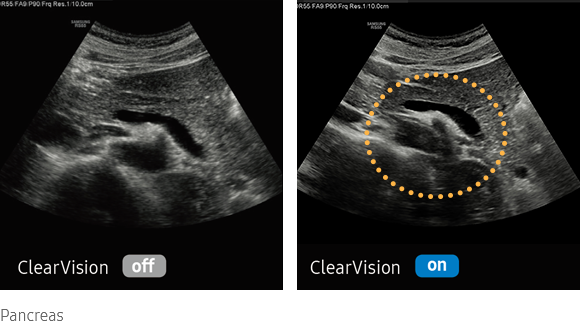

Noise reduction filter to improve 2D image quality

The noise reduction filter improves edge enhancement and creates sharper 2D images for optimal diagnostic performance. The integration of specialized Samsung technology results in a notable improvement in image quality. In addition, ClearVison provides application-specific optimization and advanced temporal resolution in live scan mode.

imaging solutions : ClearVison

Clarify blurred area to provide clearer images

HQ-Vision provides clearer images by mitigating the characteristics of ultrasound images that are slightly blurred than the actual vision.

medical diagnostics : HQ-Vision™